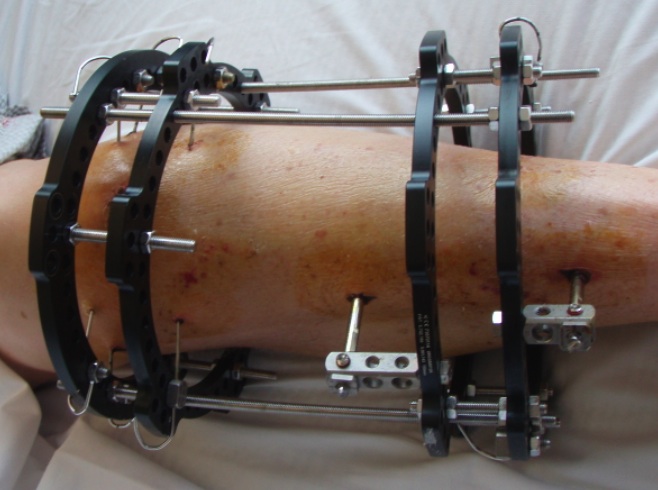

Ilizarov

Indications

Poor soft tissues

- prohibit ORIF

Non union

Infected non uniion

Malunion / deformity

Bone loss / bone transport / LLD

Concept